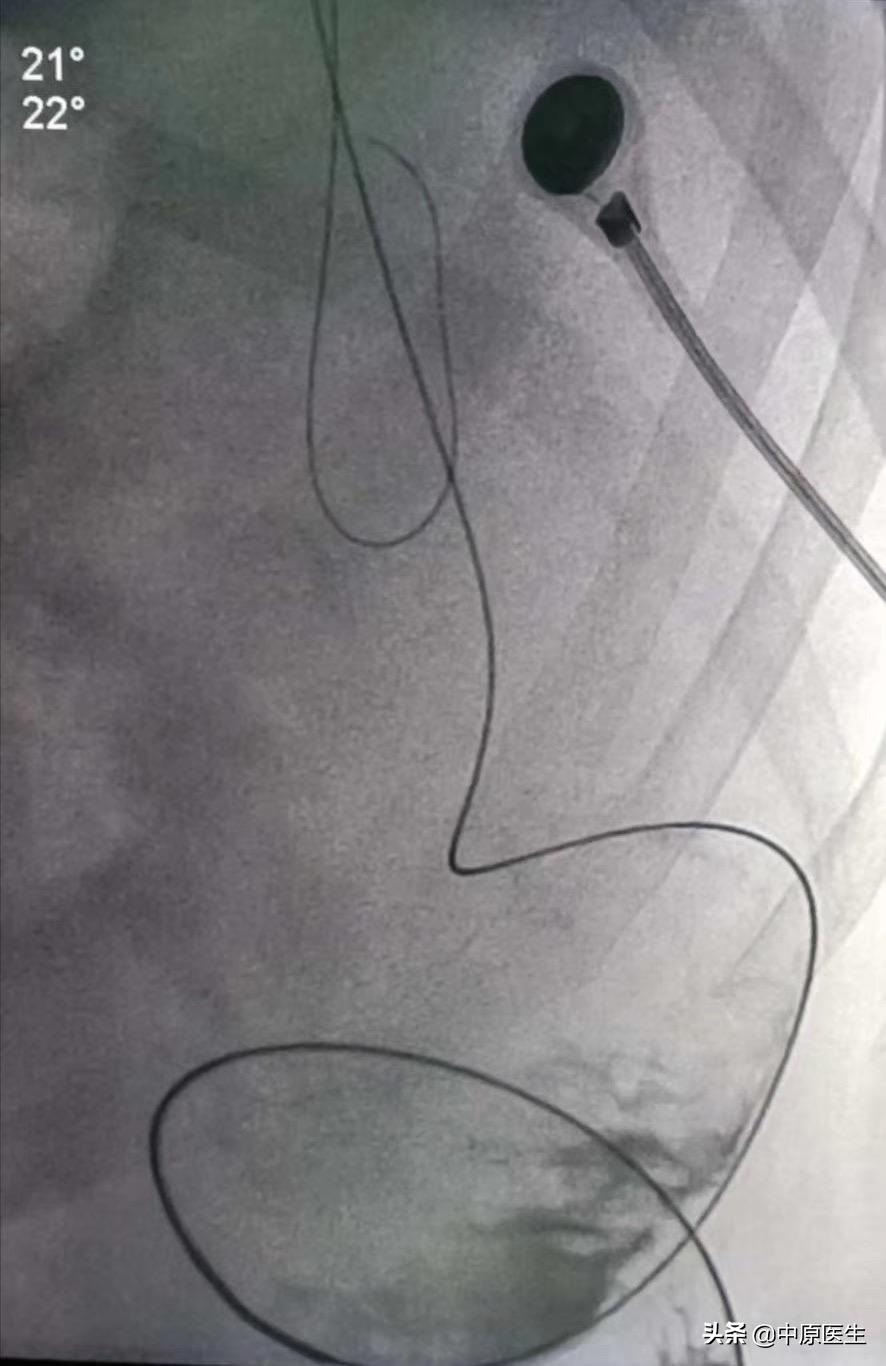

经过会诊,我们介入科刘建文教授团队决定通过介入方法帮助患者解决肿瘤引起梗阻的问题。25日,在导管室行局麻下消化道造影+降结肠球囊扩张+经肛型肠梗阻导管置入术。术中透视见腹部膨大,肠管明显扩张,膈肌上移。让患者取截石位仰卧,充分润滑、局麻后,我们送入超滑导丝、直径不到1mm的导管,反复尝试导丝通过闭塞处、送至横结肠脾曲处,但导管无法跟进,为了保留150cm的超滑导丝,将100cm的直径不到1mm导管分段剪断、依次撤出,再送入直径2mm的指引导管,再送入一根260cm的超滑加硬导丝,送至横结肠内,依次用10mm球囊、肠梗阻导管的扩张器反复扩张狭窄处,肠梗阻导管仍无法通过,再次同轴送入双导丝,应用16mm球囊多次扩张后,顺利把肠梗阻导管送至横结肠内,充盈导管头端球囊,将肠梗阻导管头端固定于降结肠梗阻处上方;淤积的肠气和部分肠液、粪便排入引流袋内,病人腹胀减轻。术中反复交换各种导丝、导管,带出不少臭屁、臭粪便。整个手术间都是不可描述的气味、手术台不忍直视。